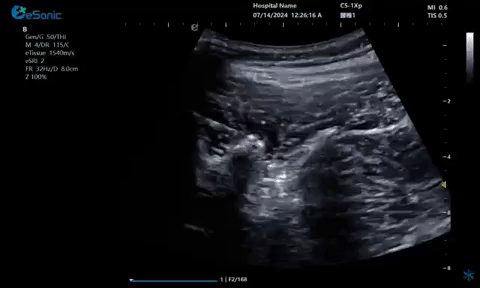

超声引导下蝶颚神经节阻滞术

大雁征-上颌动脉切面

9.gif